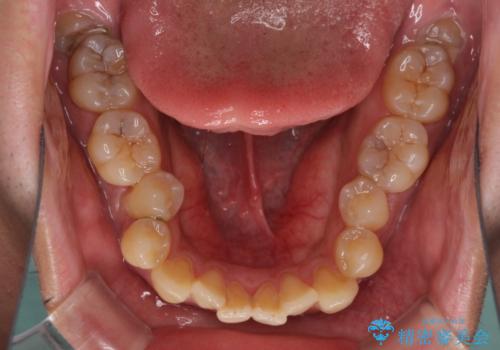

- 上下前歯の隙間と口元の出っ張った感じを気にして来院された患者様です。

上下の隙間は舌突出癖によるもので、またその癖により前歯が前方に出ている状態でした。

口元の出っ張りを改善するため、上下左右第一小臼歯4本を抜去し、ワイヤー装置にて矯正治療を行うこととしました。